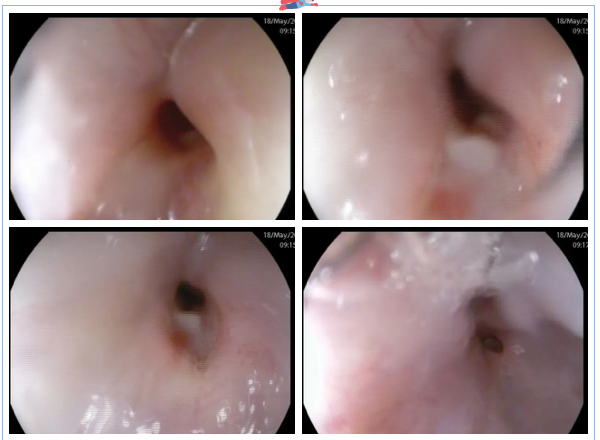

這時(shí),3診是一位懷疑食管瘺的患者,進(jìn)鏡至距門(mén)齒約25cm見(jiàn)食管管腔狹窄明顯,無(wú)法繼續(xù)進(jìn)鏡,狹窄處黏膜粗糙、色紅,可見(jiàn)潰瘍形成。嘗試給予胃營(yíng)養(yǎng)管置入,插至距門(mén)齒約35cm處阻力過(guò)大,反復(fù)嘗試后,無(wú)法留置。